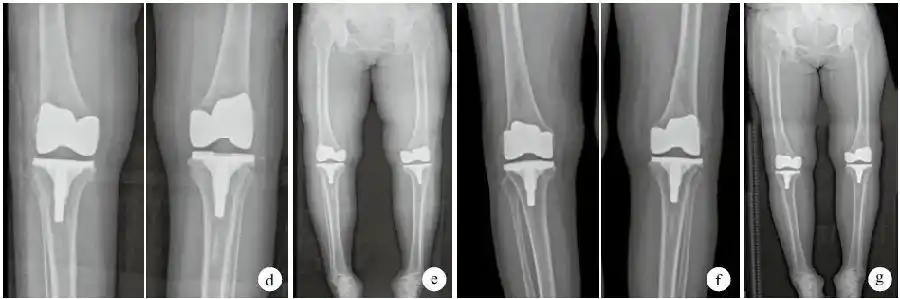

应用缩小胫骨平台截骨技术矫正膝内翻畸形的探讨